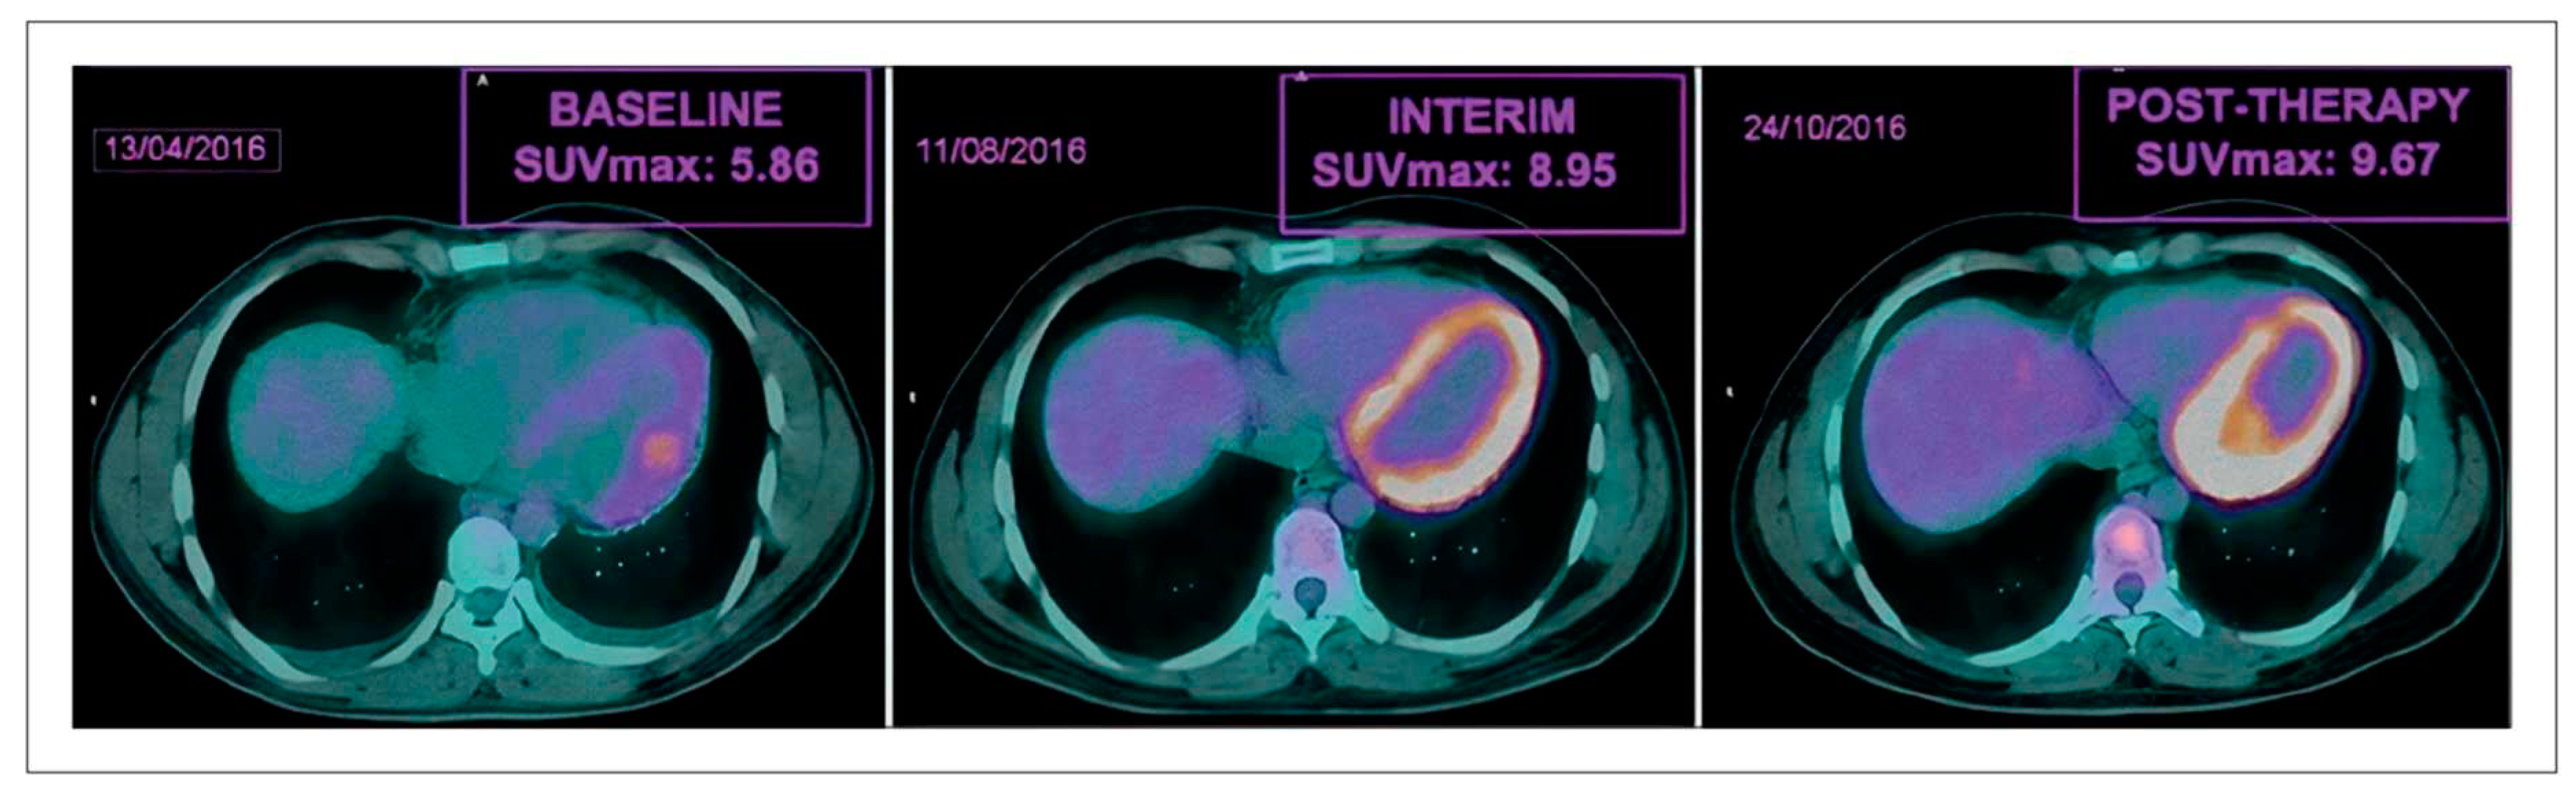

- Sarocchi, M.; Bauckneht, M.; Arboscello, E.; Capitanio, S.; Marini, C.; Morbelli, S.; Miglino, M.; Congiu, A.G.; Ghigliotti, G.; Balbi, M.; et al. An increase in myocardial 18-fluorodeoxyglucose uptake is associated with left ventricular ejection fraction decline in Hodgkin lymphoma patients treated with anthracycline. J Transl Med 2018, 16, 295. [Google Scholar] [CrossRef] [PubMed]

- Gorla, A.K.; Sood, A.; Prakash, G.; Parmar, M.; Mittal, B.R. Substantial Increase in Myocardial FDG Uptake on Interim PET/CT May Be an Early Sign of Adriamycin-Induced Cardiotoxicity. Clin Nucl Med 2016, 41, 462–463. [Google Scholar] [CrossRef] [PubMed]

- Bauckneht, M.; Ferrarazzo, G.; Fiz, F.; Morbelli, S.; Sarocchi, M.; Pastorino, F.; Ghidella, A.; Pomposelli, E.; Miglino, M.; Ameri, P.; et al. Doxorubicin Effect on Myocardial Metabolism as a Prerequisite for Subsequent Development of Cardiac Toxicity: A Translational 18F-FDG PET/CT Observation. J Nucl Med 2017, 58, 1638–1645. [Google Scholar] [CrossRef] [PubMed]

- Bauckneht, M.; Cossu, V.; Miceli, A.; Donegani, M.; Capitanio, S.; Morbelli, S.; Marini, C.; Sambuceti, G. FDG-PET Imaging of Doxorubicin-Induced Cardiotoxicity: a New Window on an Old Problem. Current Cardiovascular Imaging Reports 2019, 12. [Google Scholar] [CrossRef]